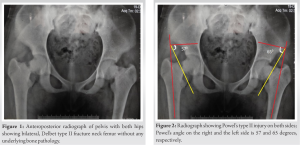

The patient had normal rheumatological, metabolic, and endocrine workup. A radiograph of the pelvis with both hips showed a Delbet type II fracture neck of the femur with preserved neck length on both sides (Fig. 1).

There was varus angulation on both sides but no significant translation of the fragments. Neck shaft angles on the right and left sides were 98° and 99°, respectively; while Powel’s angles on the right and left sides were 57° and 65°, respectively (Fig. 2).